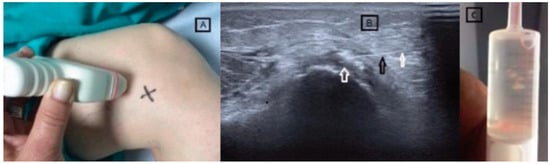

Some authors distinguish the fibers inserting on the upper aspect of the tubercle as belonging to the long tendon of the adductor magnus, differentiating them from the insertions of the medial gastrocnemius and the medial collateral ligament of the knee [6,7]. Despite this, the close proximity of the MCL fibers and the ischiochondylar portion of the adductor magnus can complicate the differential diagnosis. Magnetic resonance imaging (MRI) plays a crucial role in specifying the location and type of calcifications, which facilitates a differential diagnosis [13] (Figure 1).

Figure 1. Diagram of a coronal section of the knee showing the area of insertion of the magnus adductor tendon in the internal femoral condyle and corresponding image in MRI (arrow).